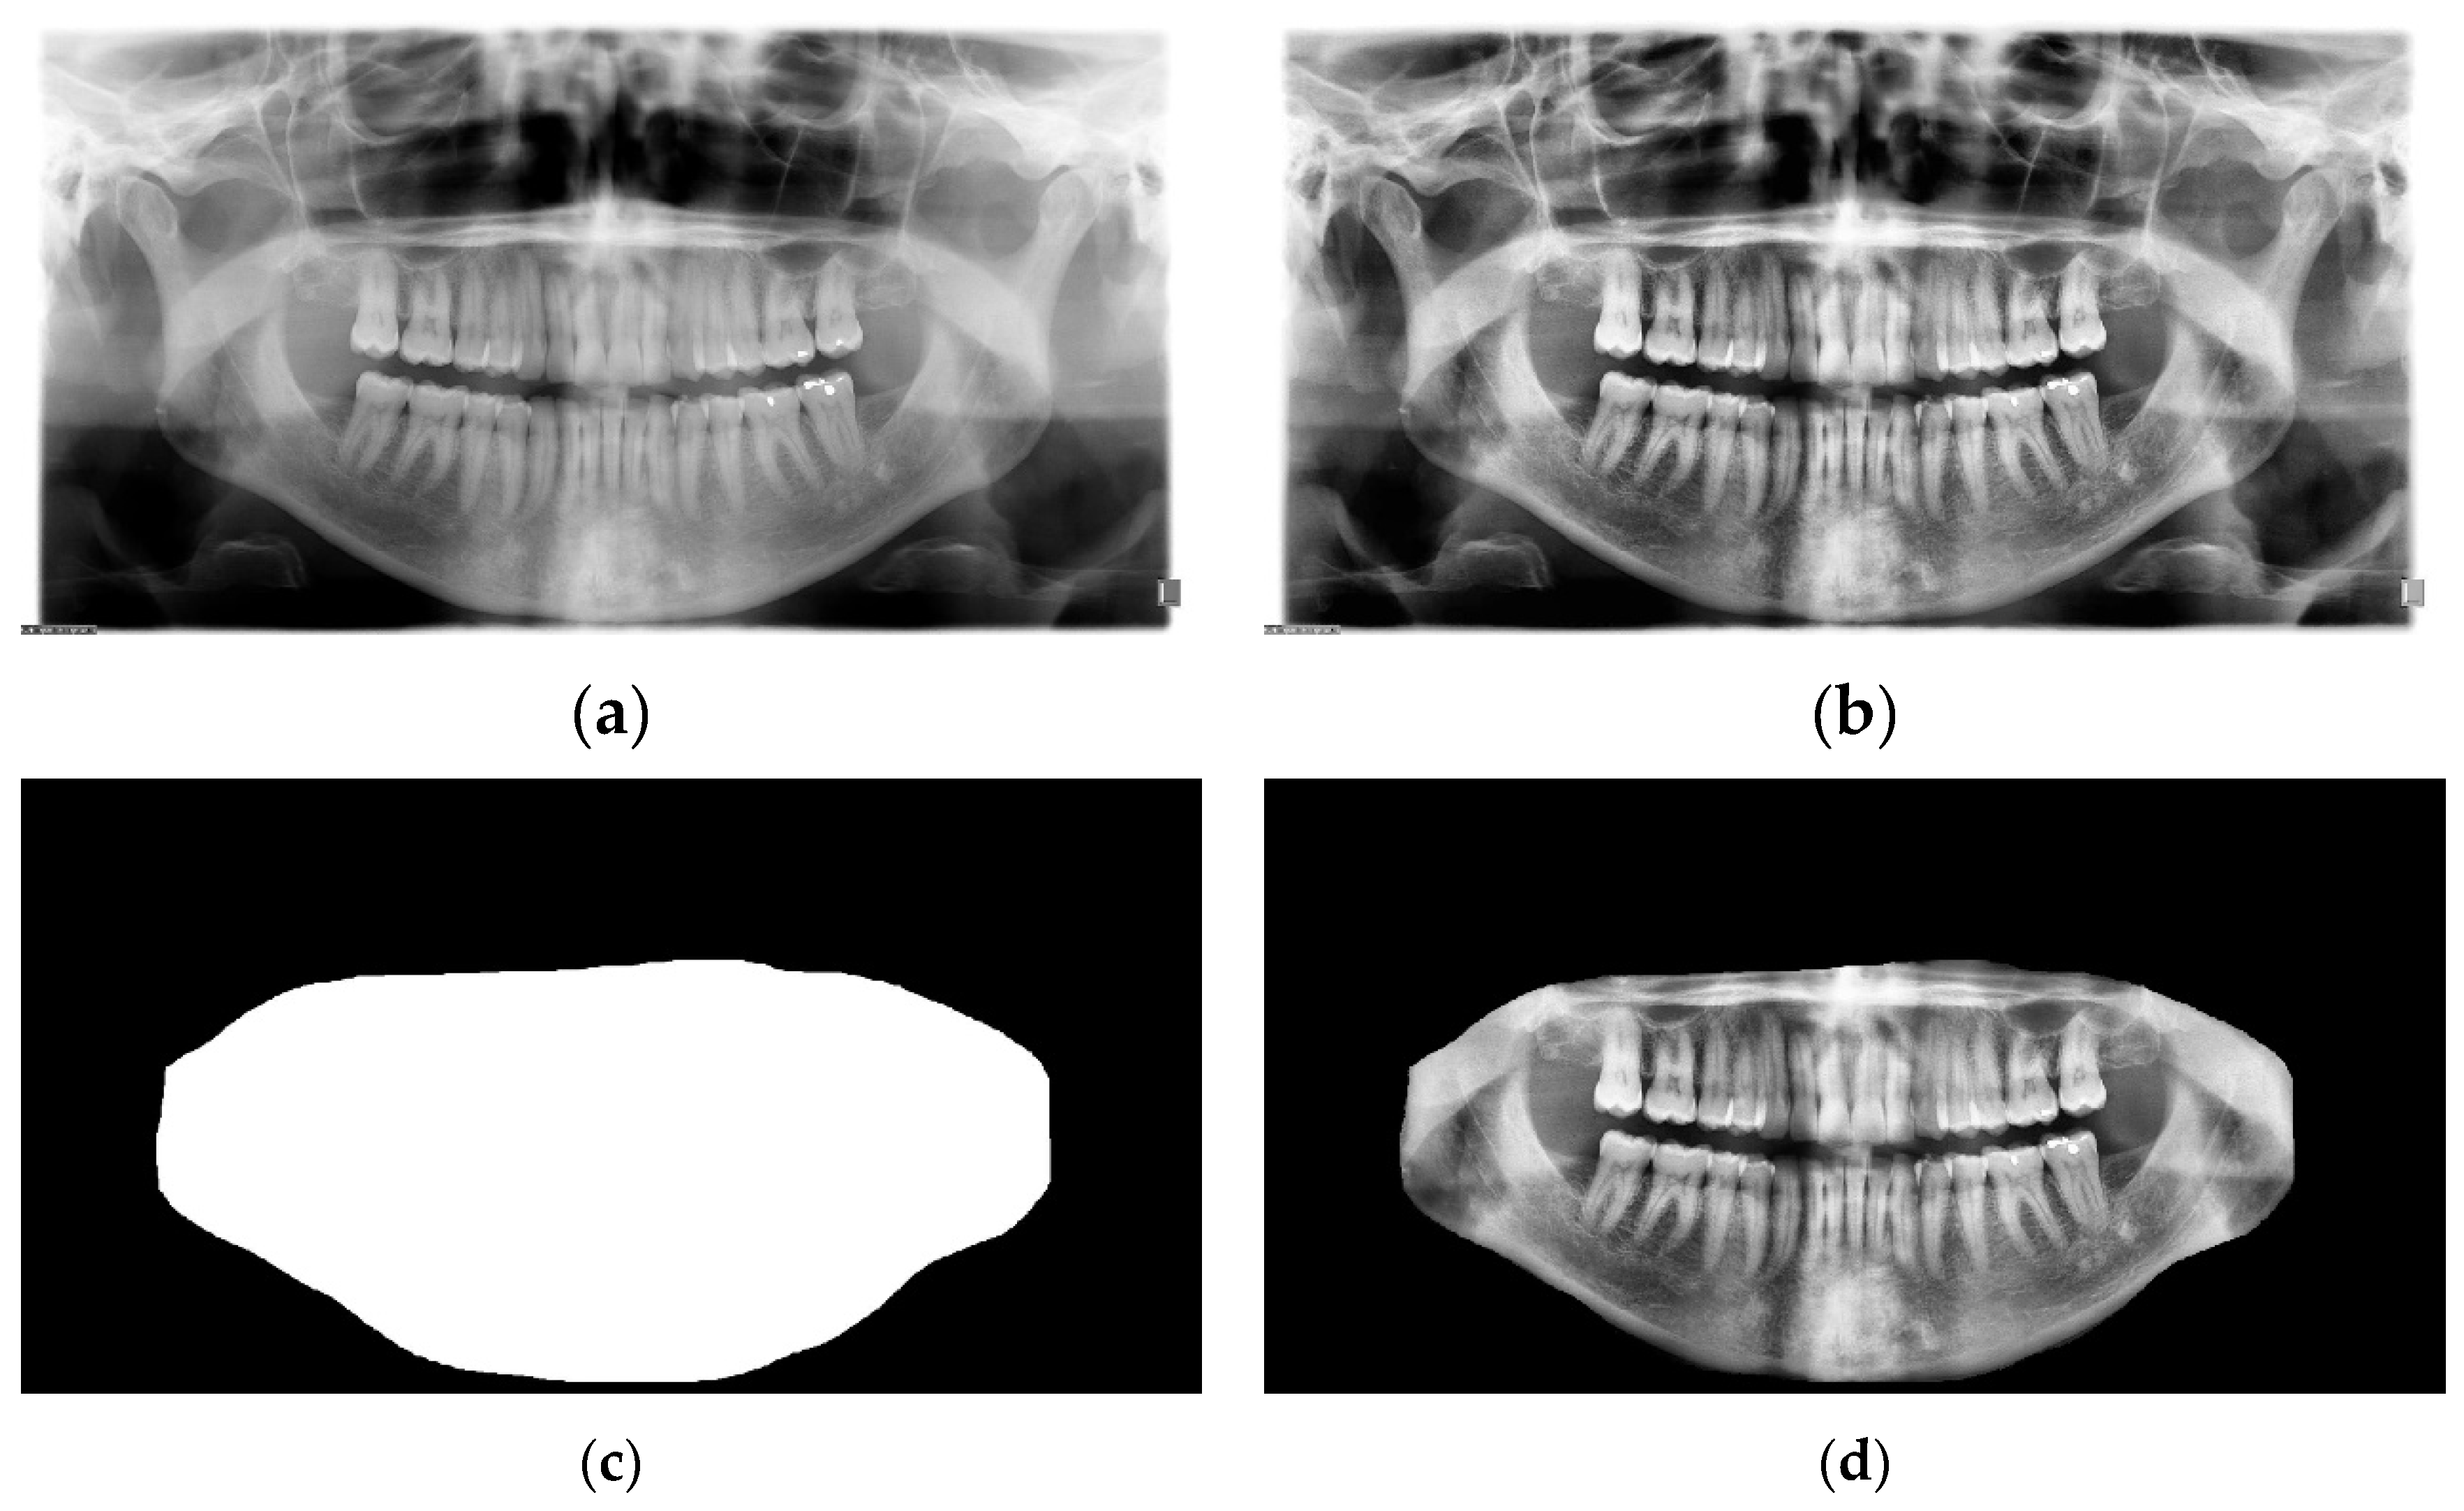

The preprocessing process is as follows: Contrast Limited Adaptive Histogram Equalization (CLAHE) [41] was applied to the images to enhance the image features. The contrast enhancement process had a major impact on the visibility of the images. Figure 6b and Figure 6a show the original and enhanced image, respectively. To further yield better performance from the model, the maxillomandibular mask shown in Figure 6c was used by applying an AND operation to the maxillomandibular mask with the preprocessed image to get only the ROI that includes the teeth shown in Figure 6d. Finally, the processed radiograph shown in Figure 6d and its corresponding ground truth mask shown in Figure 5d were resized to 512 ×

256. The preprocessing was applied to all examples in the dataset.

Figure 6. The preprocessing steps for the dataset. (a) is the original image, (b) after applying the Contrast Limited Adaptive Histogram Equalization. (c) is the maxillomandibular mask highlighting the ROI, and (d) is the final image after doing an AND operation on (b) with (c).